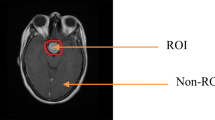

The near-lossless compression technique has better compression ratio than lossless compression technique while maintaining a maximum error limit for each pixel. It takes the advantage of both the lossy and lossless compression methods providing high compression ratio, which can be used for medical images while preserving diagnostic information. The proposed algorithm uses a resolution and modality independent threshold-based predictor, optimal quantization (q) level, and adaptive block size encoding. The proposed method employs resolution independent gradient edge detector (RIGED) for removing inter-pixel redundancy and block adaptive arithmetic encoding (BAAE) is used after quantization to remove coding redundancy. Quantizer with an optimum q level is used to implement the proposed method for high compression efficiency and for the better quality of the recovered images. The proposed method is implemented on volumetric 8-bit and 16-bit standard medical images and also validated on real time 16-bit-depth images collected from government hospitals. The results show the proposed algorithm yields a high coding performance with BPP of 1.37 and produces high peak signal-to-noise ratio (PSNR) of 51.35 dB for 8-bit-depth image dataset as compared with other near-lossless compression. The average BPP values of 3.411 and 2.609 are obtained by the proposed technique for 16-bit standard medical image dataset and real-time medical dataset respectively with maintained image quality. The improved near-lossless predictive coding technique achieves high compression ratio without losing diagnostic information from the image.